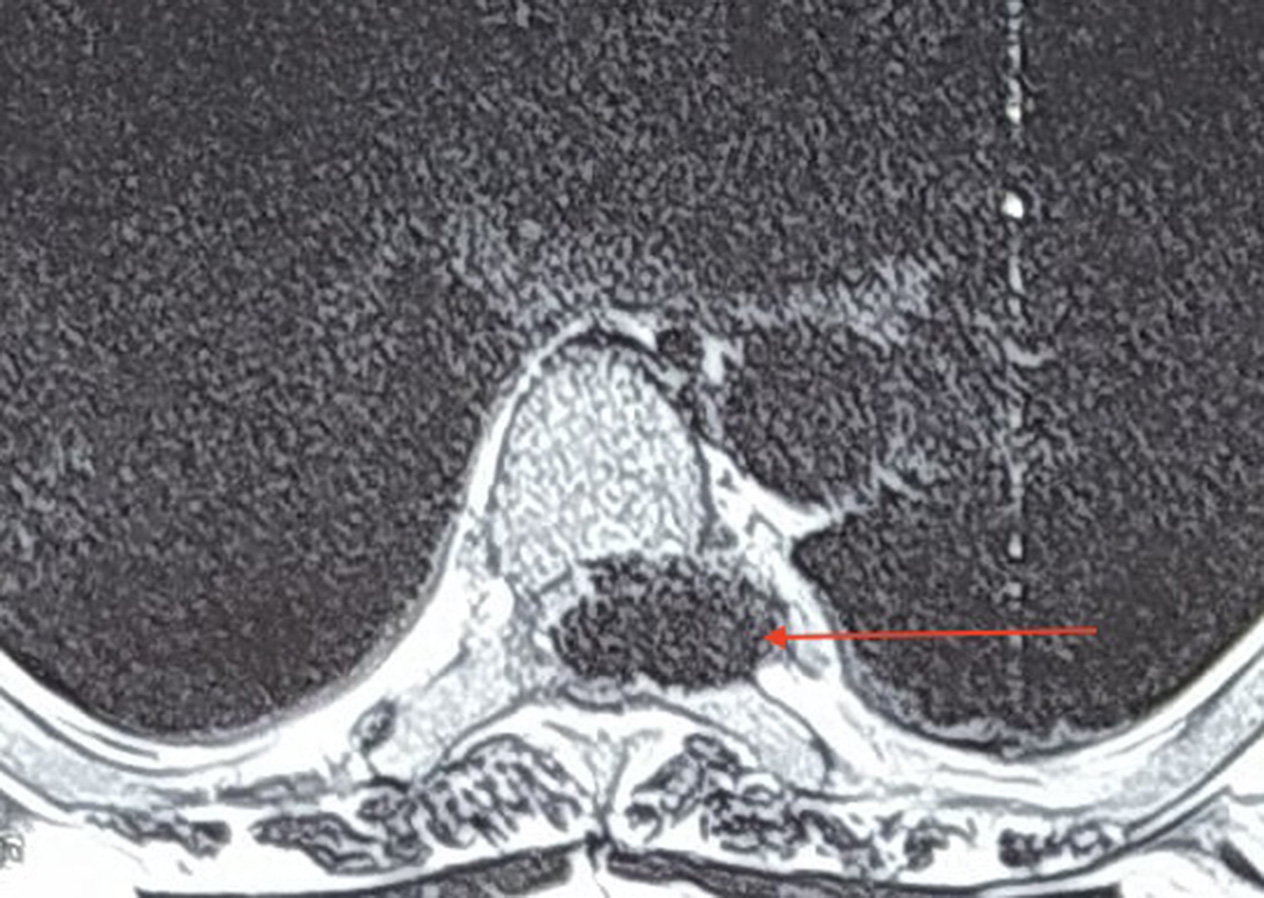

He had bladder and bowel incontinence. The remainder of his physical examination was within normal limits. Magnetic resonance imaging (MRI) of his spine revealed a T1 hyperintense and T2 hypointense lesion at the level of D4 vertebra. (Figures 1A, 1B, 2A and 2B). The lesion was homogeneously enhancing on contrast and was located intradurally and extramedullary on the left side. A differential diagnosis of metastatic lesion was made and thorough metastatic workup done, which however failed to show any primary tumour elsewhere.

Fig. 1B. Axial T2-weighted image showing a hypointense dumbbell-shaped lesion on left side with significant cord compression extending transforaminally (red arrow)